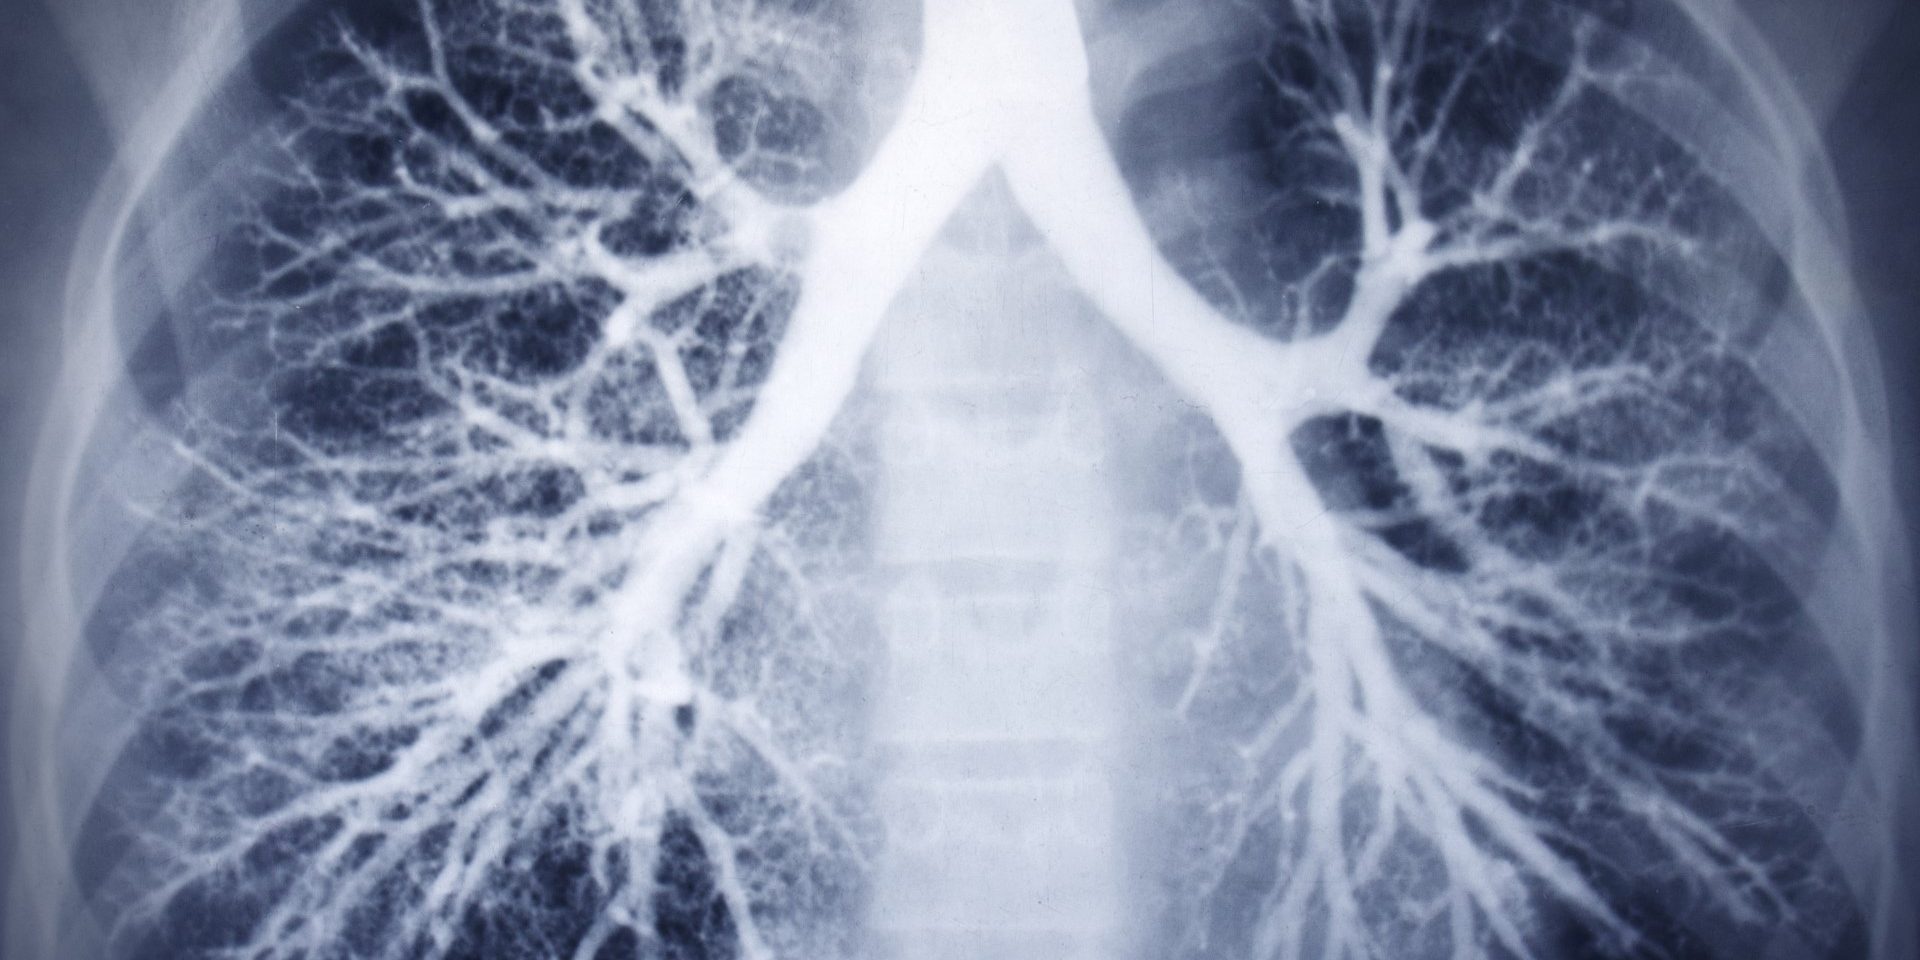

Autogene drainage is een onderdeel van een breder palet aan ademhalingskinesitherapie. Het is bedoeld om de longen vrij te maken van overtollig slijm, bronchiale weerstand op te bouwen en de inspanningscapaciteit te verhogen.

Het vrijmaken van de longen is belangrijk bij onder meer mucoviscidose of infectieziekten zoals acute en chronische longontstekingen, bronchitis en bronchiolitis. Ook tijdens revalidatie na besmetting met het coronavirus COVID-19 heeft het haar nut bewezen.

Bij autogene drainage helpen we de patiënt om de longen vrij te maken. Dat gebeurt door zelf het slijm te lokaliseren, er goed doorheen te ademen om het slijm los te maken en het efficiënt op te hoesten.